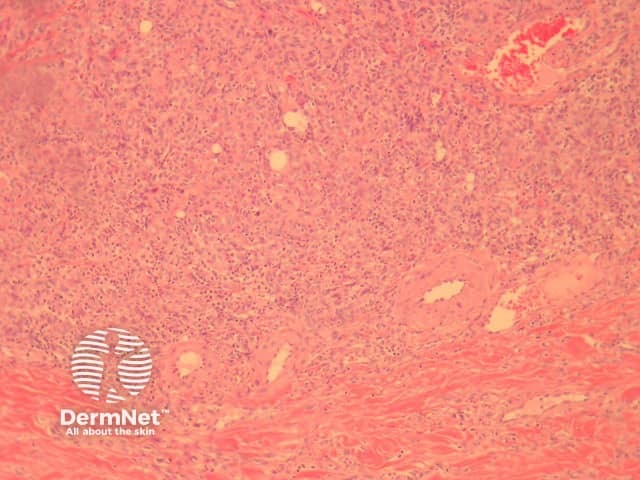

In erysipelas, there is impressive subepidermal oedema (figure 1) underlying an uninvolved epidermis. There is striking vascular ectasia. Beneath these changes there is initially neutrophilic infiltration and later mature but inflamed granulation tissue in the deep dermis/subcutis (figure 2). Abscess formation is not a feature.

Figure 2